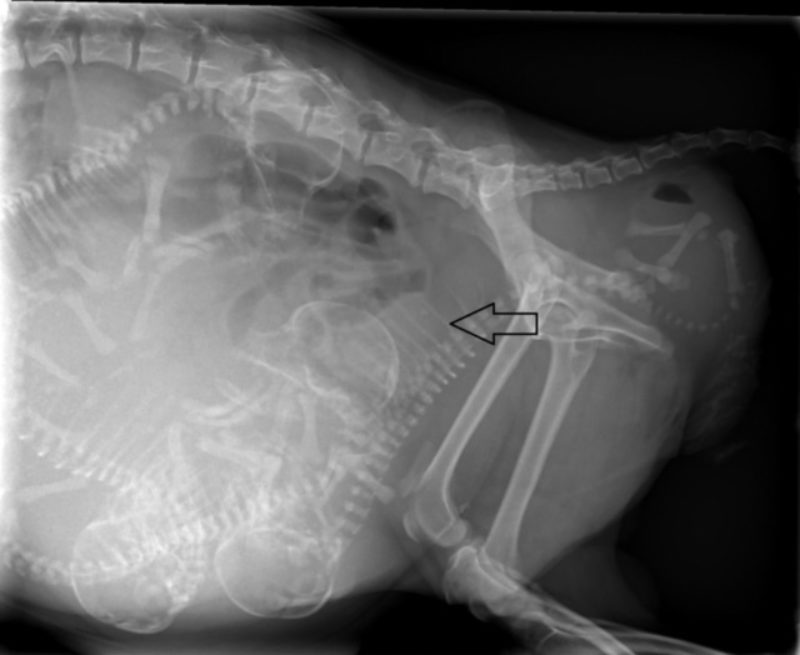

Letzteres ist gerade bei Chihuahuas mit ihren großen, runden Köpfen durchaus eine Möglichkeit, die einem in einem solchen Moment in den Sinn kommt. Wir entschieden uns, Bailey zu uns in die Praxis bringen zu lassen. Sie selbst war in guter Verfassung, ihre Wehen kamen kräftig in regelmäßigen Intervallen. Ein Röntgenbild brachte jedoch ans Licht, weswegen die Geburt nicht in die Gänge kommen wollte: Der erste Welpe befand sich in Hinter-Endlage auf dem Rücken liegend. An sich ist eine Geburt mit den Hinterbeinen voran beim Hund möglich, doch die Drehung des Fetus auf den Rücken verhinderte, dass sich sein Körper dem Geburtsweg seiner Mutter anpassen konnte. Er steckte fest. Von vaginal ließen sich seine Füßchen greifen und sein Körper in eine halbwegs aufgerichtete Position bringen – bei einer Mutter in der Größe eines Chihuahua kein leichtes Unterfangen – doch mit jeder Wehe drehte er sich wieder in die alte Lage zurück.